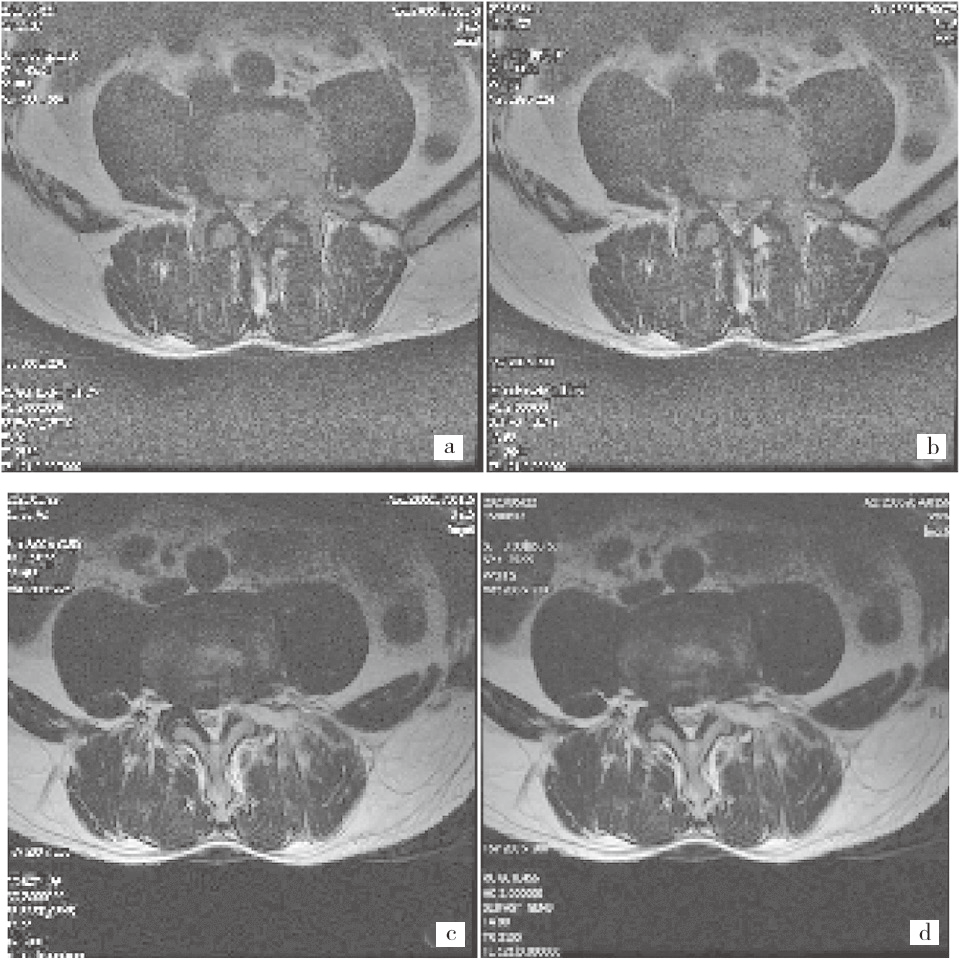

82 例 LDH 患者术前 JOA 评分为(13.64±3.01)分,术后 3 个月 JOA 评分为(26.74±3.25)分。术后 3 个月 LDH 患者的 JOA 评分高于术前(t = 26.779,P < 0.05)。LDH 患者手术前后 MRI 影像学特征见图 1。

注:患者男,47 岁,临床诊断为 LDH。a 为 L4~ 5 椎间盘左后下方脱出,术前椎管径为 0.5 cm;b 为 L4~ 5 椎间盘左后下方脱出;c 为术后椎间盘,椎管径为 1.25 cm;d 为术后 L4~ 5 椎间盘

图 1 LDH 微创消融手术前后 MRI 影像学特征